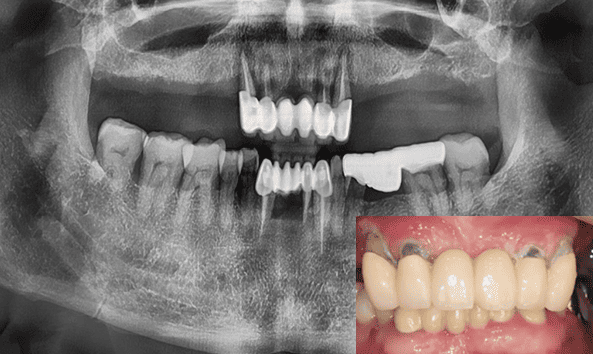

일반틀니 + 임플란트 틀니

전체 임플란트 + 임플란트 틀니

- 23.10

* 임플란트 시술 시 교합이상, 신경손상, 염증 등의 부작용이 발생할 수 있습니다.

* 개인의 구강 및 치아상태에 따라 치료방법과 수가가 변동될 수 있습니다.

* 해당 사례는 의료법 제56조 2항을 준수하여 작성되었습니다.

* 본원에서 진료받은 환자이며 전후 사진의 인물이 동일인임을 밝힙니다.